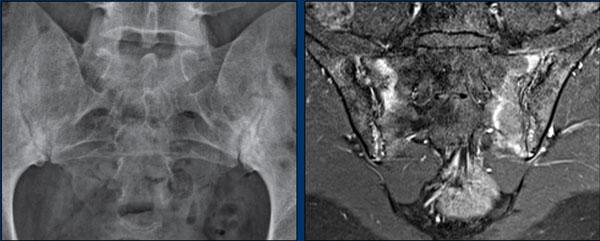

Hình ảnh X-quang khung chậu của bệnh nhân viêm khớp do lao tại khớp háng trái.

Có hẹp khe khớp kín đáo kèm theo xơ cứng dưới sụn tại khớp háng trái.

Các dấu hiệu X-quang này không đặc hiệu và rất có thể là biểu hiện của thoái hóa khớp.

Tiếp tục xem hình ảnh MRI…

Điều bất ngờ với tất cả mọi người là có nhiều ổ áp-xe.

Khi hình thành áp-xe lan rộng như vậy trong khi biểu hiện lâm sàng lại tối thiểu, cần luôn nghĩ đến viêm khớp do lao.

Chẩn đoán viêm khớp do lao được xác lập bằng chọc hút dịch khớp.

MRI

MRI chuỗi xung T1W sau tiêm thuốc tương phản từ của cùng bệnh nhân cho thấy bờ khớp cùng chậu không đều do bào mòn.

Có ngấm thuốc ở xương dưới sụn và phù nề tủy xương.

Không có tràn dịch khớp.

Thuốc tương phản từ tiêm tĩnh mạch không nhất thiết phải sử dụng để chẩn đoán viêm khớp cùng chậu.

Cuộn qua các hình ảnh MRI và so sánh với các dấu hiệu trên X-quang (hình ảnh cuối cùng).